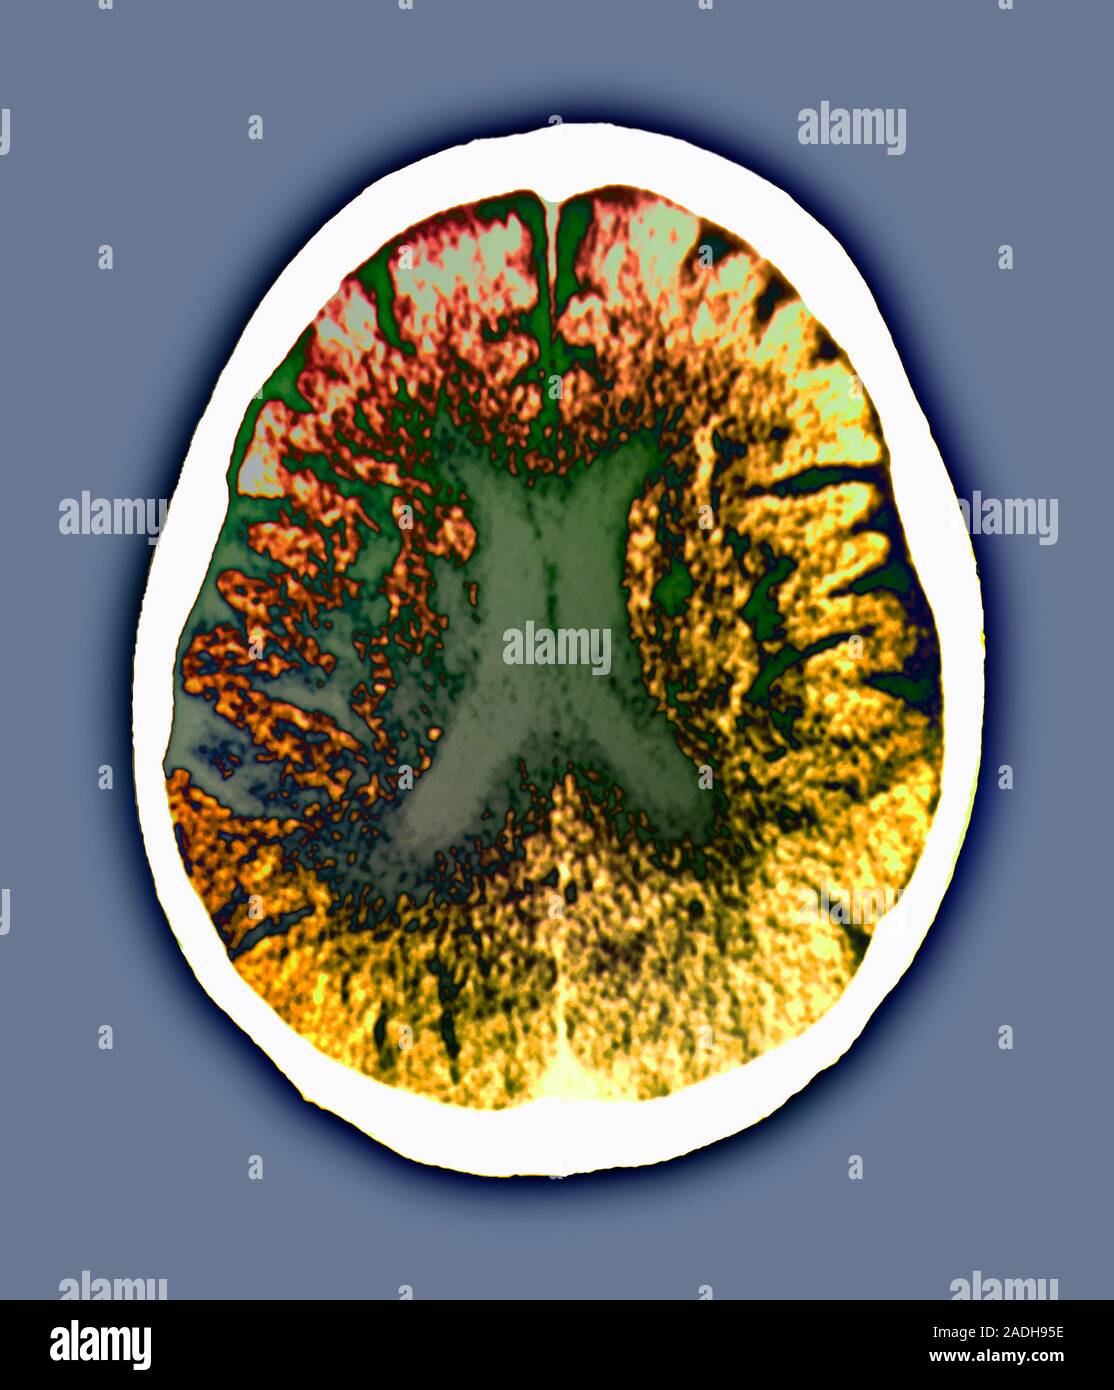

La enfermedad de Binswanger, también llamada encefalopatía subcortical o demencia vascular subcortical, es un tipo de demencia poco habitual que se caracteriza por la afectación de los pequeños vasos sanguíneos situados en la región subcortical del cerebro (demencia vascular)[1] y la aparición en las pruebas de imagen como la resonancia magnética nuclear de rarefacción de la sustancia blanca (leucoaraiosis) y múltiples infartos lacunares subcorticales.[2][3] Los primeros síntomas suelen aparecer entre los 54 y 64 años y consisten generalmente en deterioro cognitivo, más adelante es habitual que se produzca accidente cerebrovascular.[4][5]